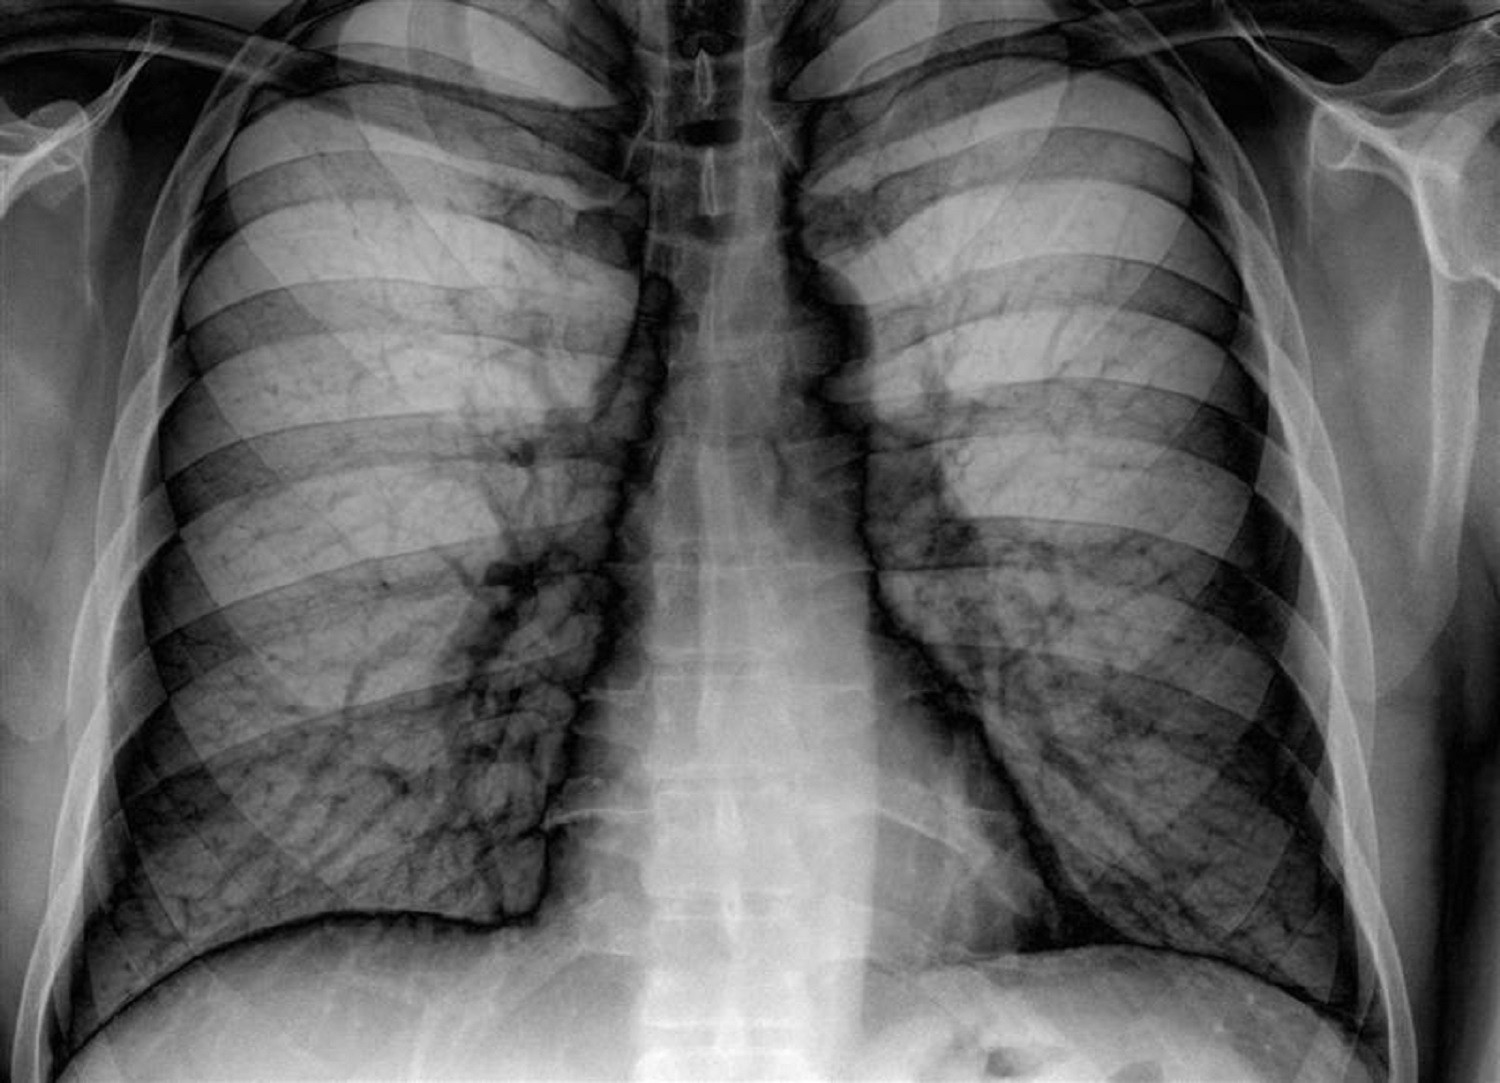

Ένα νέο σύστημα τεχνητής νοημοσύνης της Google Health, θυγατρικής της Google στο πεδίο της «έξυπνης» υγείας, μπορεί να μελετήσει ακτινογραφίες πνευμόνων και να βγάλει συμπεράσματα εξίσου αξιόπιστα με εκείνα των έμπειρων ακτινολόγων.

Οι ερευνητές, που έκαναν τη σχετική δημοσίευση στο Radiology της Ακτινολογικής Εταιρείας της Βόρειας Αμερικής, εκπαίδευσαν το σύστημά τους τροφοδοτώντας το με περισσότερες από 860.000 ακτινογραφίες. Η ακτινογραφία πνευμόνων είναι από τις συχνότερες εξετάσεις παγκοσμίως, όμως έχει ορισμένους περιορισμούς.

Οι δοκιμές του συστήματος από επιτροπή ακτινολόγων έδειξαν ότι τα καταφέρνει τουλάχιστον εξίσου καλά με τους γιατρούς στην ανίχνευση διαφόρων προβλημάτων (διάγνωση καταγμάτων, οζιδίων, όγκων, πνευμοθώρακα κ.ά.).